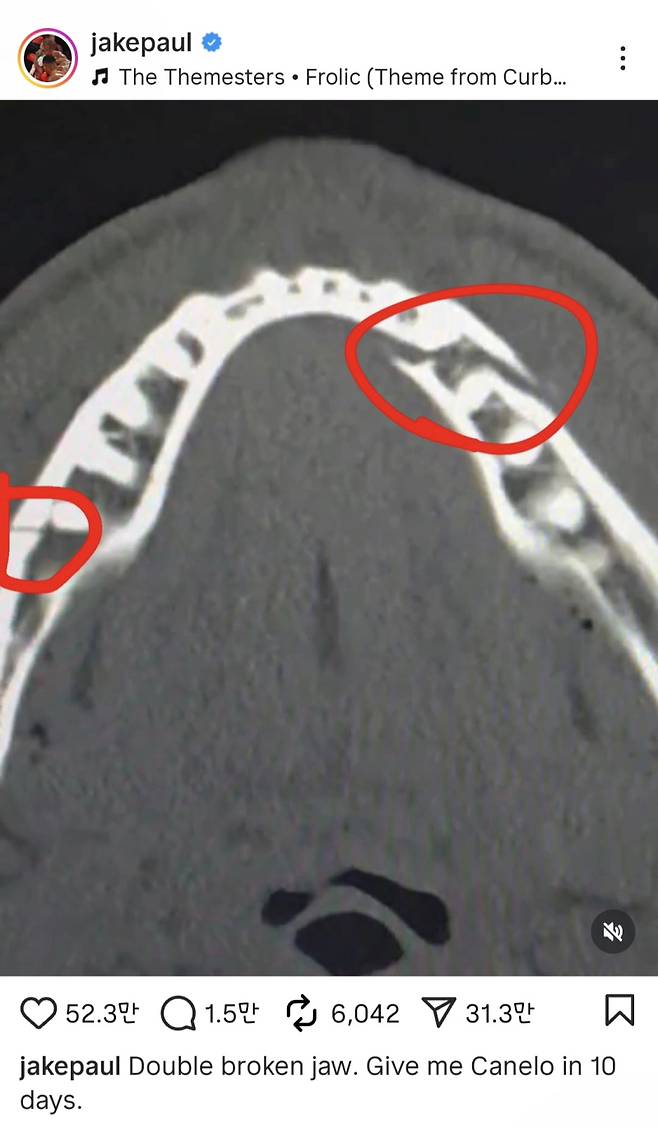

폴은 21일(한국시간) 자신의 소셜미디어(SNS)에 턱부위 엑스레이 사진을 올리며 "턱 두 곳이 골절됐다"고 밝혔다.

하지만 폴 역시 특유의 자신감을 잃지 않았다. 폴은 SNS에 "10일 뒤에 카넬로 알바레스를 데려와라(붙여달라)"고 말했다. 알바레스는 프로 복싱 전적 63승 2무 3패를 기록 중인 통합 챔피언이다.

물론, 이는 농담이다. 턱뼈가 두 곳이나 부러진 폴은 곧 병실에서 찍은 사진을 올리며 "통증이 심하고 몸이 뻣뻣하다. 7일 동안은 유동식만 먹어야 한다"라며 당분간은 치료가 필요한 상황임을 언급했다. 그러면서도 그는 "응원해줘서 고맙다. 난 괜찮다"라며 팬들을 안심시켰다.